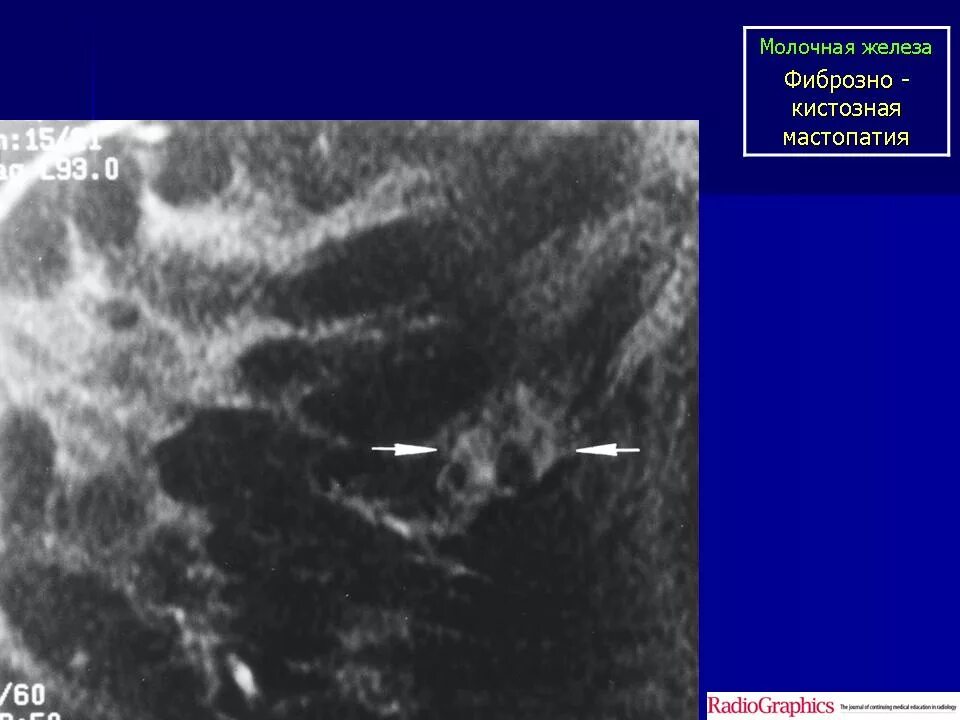

Фиброматоз мягких